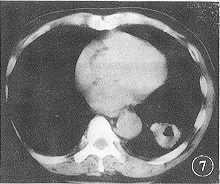

图7 左下肺低分化鳞癌。瘤体出现坏死,偏心空洞,PCNA表达面积为14523.88 μm2

当肿瘤细胞的增殖速度超过肿瘤血管内皮的增殖速度时,必然导致肿瘤血循环相对不足,以致肿瘤缺氧坏死形成空洞。本组21例(13例为鳞癌)有癌性坏死和空洞者的PCNA表达面积明显高于无癌性坏死和空洞者(图7)。提示出现坏死和空洞的肿瘤生长更迅速,恶性度更高。临床追踪发现有癌性坏死和空洞者,复发早,生存期短。